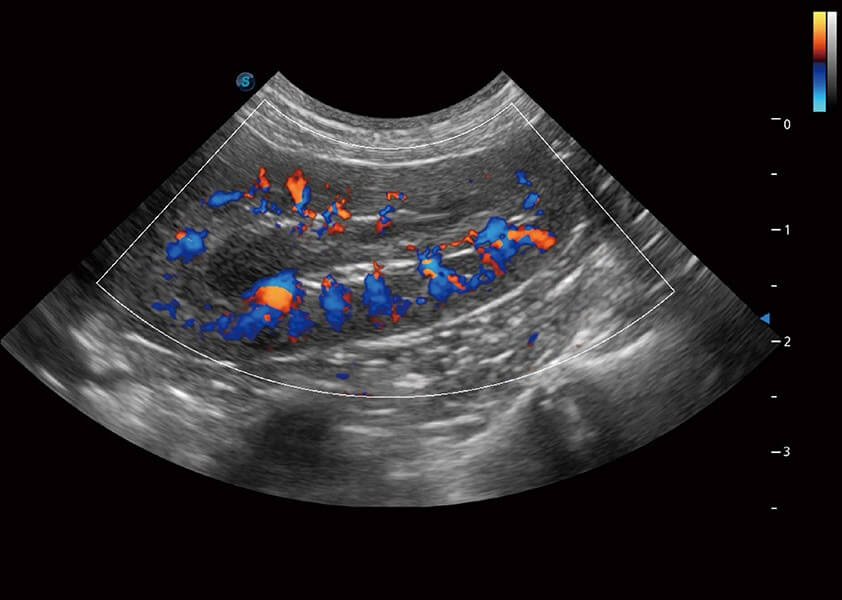

ProPet 60 作为一款高端台式动物超声设备,为动物医生的日常诊断提供了一系列贴合动物临床需求、解决临床实际问题的高级成像功能。凭借全系列高清探头,满足医生对腹部、心脏、生殖、浅表、肌骨等成像的所有需求,切实帮助您提升检查效率,提高诊断信心。

动物是人类最亲密的朋友和最值得信赖的伙伴。乐玩lewin国际也一直致力于探索动物专用的超声影像解决方案。 全新推出的ProPet系列,是乐玩lewin国际在动物超声影像智能化、专业化、精准化的一次跨越式革新。动物不能用言语来表述自己的不适,通过超声影像,ProPet系列搭建了动物医生与不同物种沟通的“桥梁”,为动物医生注入了“治愈之力”。